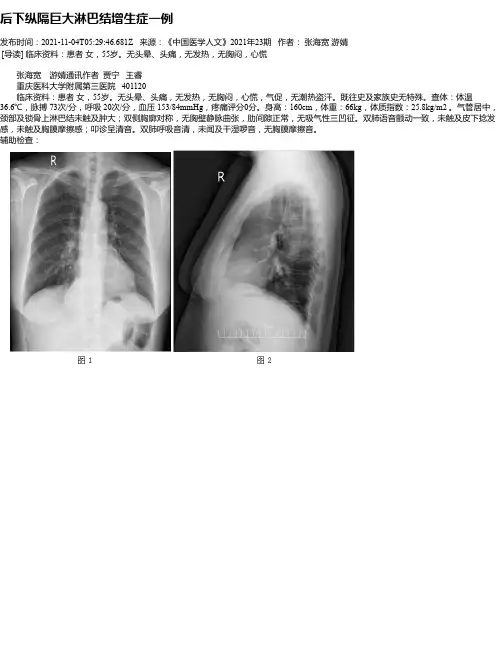

后下纵隔巨大淋巴结增生症一例发布时间:2021-11-04T05:29:46.681Z 来源:《中国医学人文》2021年23期作者:张海宽游婧[导读] 临床资料:患者女,55岁。

无头晕、头痛,无发热,无胸闷,心慌张海宽游婧通讯作者贾宁王睿重庆医科大学附属第三医院 401120 临床资料:患者女,55岁。

无头晕、头痛,无发热,无胸闷,心慌,气促,无潮热盗汗。

既往史及家族史无特殊。

查体:体温36.6℃,脉搏 73次/分,呼吸 20次/分,血压 153/84mmHg,疼痛评分0分。

身高:160cm,体重:66kg,体质指数:25.8kg/m2 。

气管居中,颈部及锁骨上淋巴结未触及肿大;双侧胸廓对称,无胸壁静脉曲张,肋间隙正常,无吸气性三凹征。

双肺语音颤动一致,未触及皮下捻发感,未触及胸膜摩擦感;叩诊呈清音。

双肺呼吸音清,未闻及干湿啰音,无胸膜摩擦音。

辅助检查:胸部DR示:胸腹交界区后下纵隔圆形软组织密度肿块影,直径约9.0cm,边界清晰,考虑占位性病变可能大,如图1、2所示。